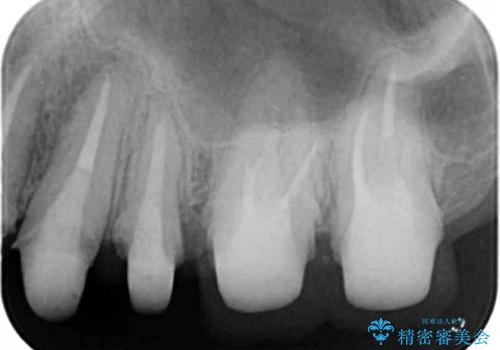

ここの歯の状態を精密に検査し、根管治療、セラミック治療、インプラント治療を含む総合的な歯科治療を計画します。